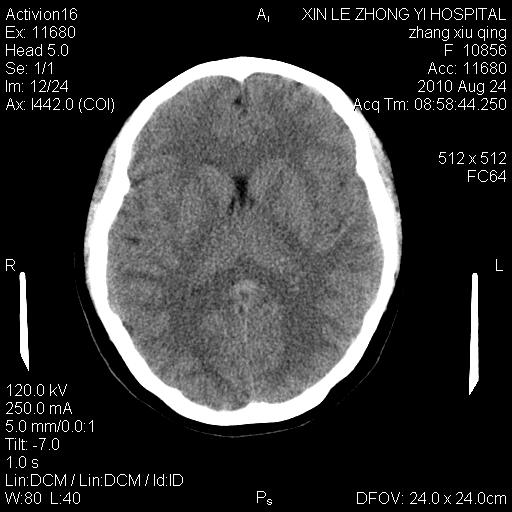

标题: CT28569:看看鞍上池正常吗

女 24 偶有头晕

未见明显异常,必要时可作mri

没什么!只是扫描层面与听眦线不平行

伪影干扰下,所见无水肿、无占位,建议定期复查。